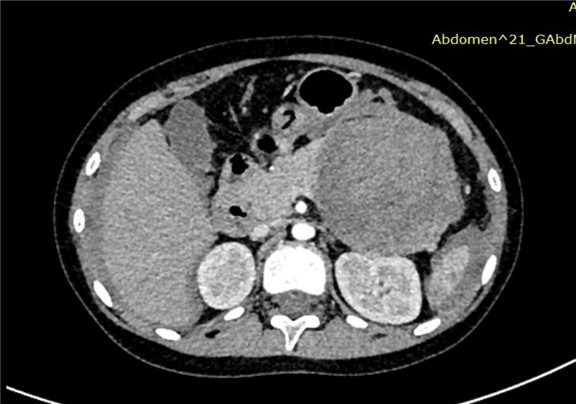

上腹部增强CT:胰尾部占位性病变,考虑胰腺尾部肿瘤并破裂出血,以胰母细胞瘤可能性大,不除外胰腺实性假乳头状瘤,肝周积液、积血,符合肿瘤破裂所致。

术前CT检查:

动脉期

静脉期